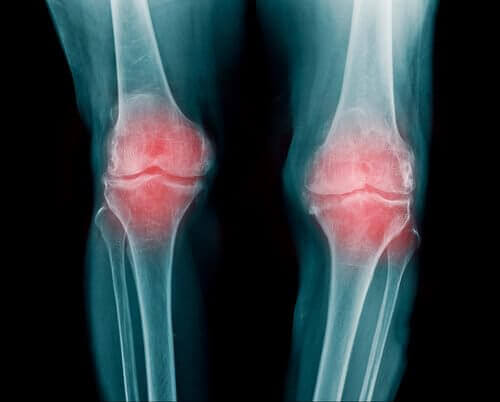

Vet du vilka livsmedel som motverkar artros? Dina leder skyddar dina kondyler och har en fundamental roll i rörelsen av dina övre och undre extremiteter. Att överanvända dem kan ge upphov till olika sjukdomar, som exempelvis artros.

Mellan varje led finns brosk som motverkar att dina ben gnuggas mot varandra. Med tidens gång kommer brosket dock minska, vilket kan leda till smärta och inflammation. Din rörelse kommer därför reduceras kraftigt och även din frihet att göra olika aktiviteter.

Smärtan vid artros uppstår p.g.a. inflammatoriska processer och inte för att vävnaden bryts ned. Svullnaden är dock huvudreaktionen på nedbrytning av cellerna. Trots detta finns det vissa perioder av artros som inte är smärtsamma (förutom i vissa fall där obehaget uppstår från ingenting).